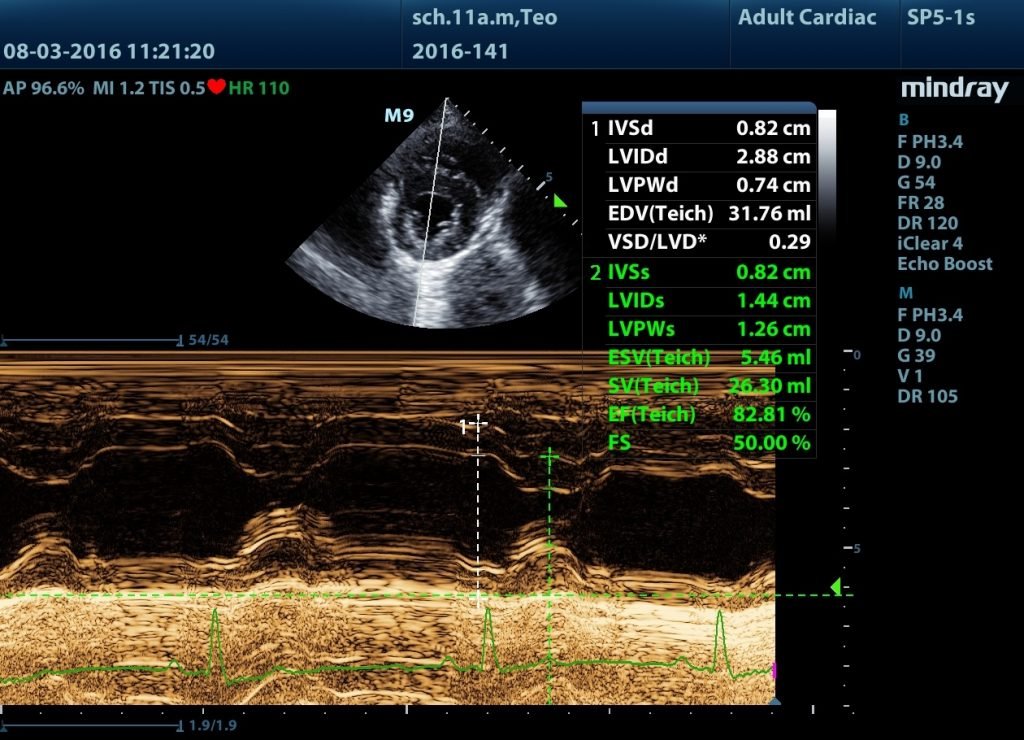

Ecografía cardiaca en pequeños animales

Fechas: 28 y 29 de octubre de 2020. Horario: miércoles y jueves de 9:30h a 14:00h (sesiones teóricas) y de 15:30h a 19:00h (sesiones prácticas). Impartido por: Susana Serrano Sobrino Responsable de la especialidad de Anestesia[…]